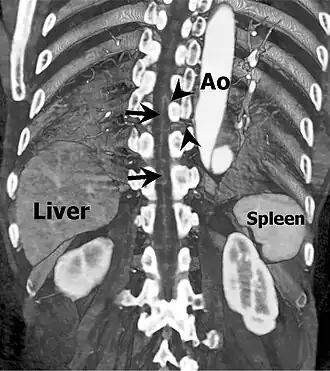

Артерия Адамкевича (также называемая артерия поясничного утолщения; большая передняя радикуломедуллярная артерия) — кровоснабжает нижнюю часть спинного мозга (начиная с позвонка от Т6 — T10). Анастомозирует с передней спинальной артерией спинного мозга.[1] Названа в честь польского врача и паталогоанатома Альберта Войцеха Адамкевича.

Имеет диаметр от 0,8 до 2мм[1][3]. Может ответвляться от спинного ответвления дорсальной ветви одной из межрёберных артерий (обычно в пределах от 5--й до 11й), подрёберной артерии или одной из поясничных (чаще всего из первой левой)[4][1]. Поднимается по средней сагиттальной передней поверхности спинного мозга, обычно на расстояние меньше двух с половиной позвонков, при анастомозе с передней спинальной артерией принимает характерный «шпилечный поворот», в остальном имеет прямое течение по сравнению с более извилистой передней радикуломедуллярной веной.[3]